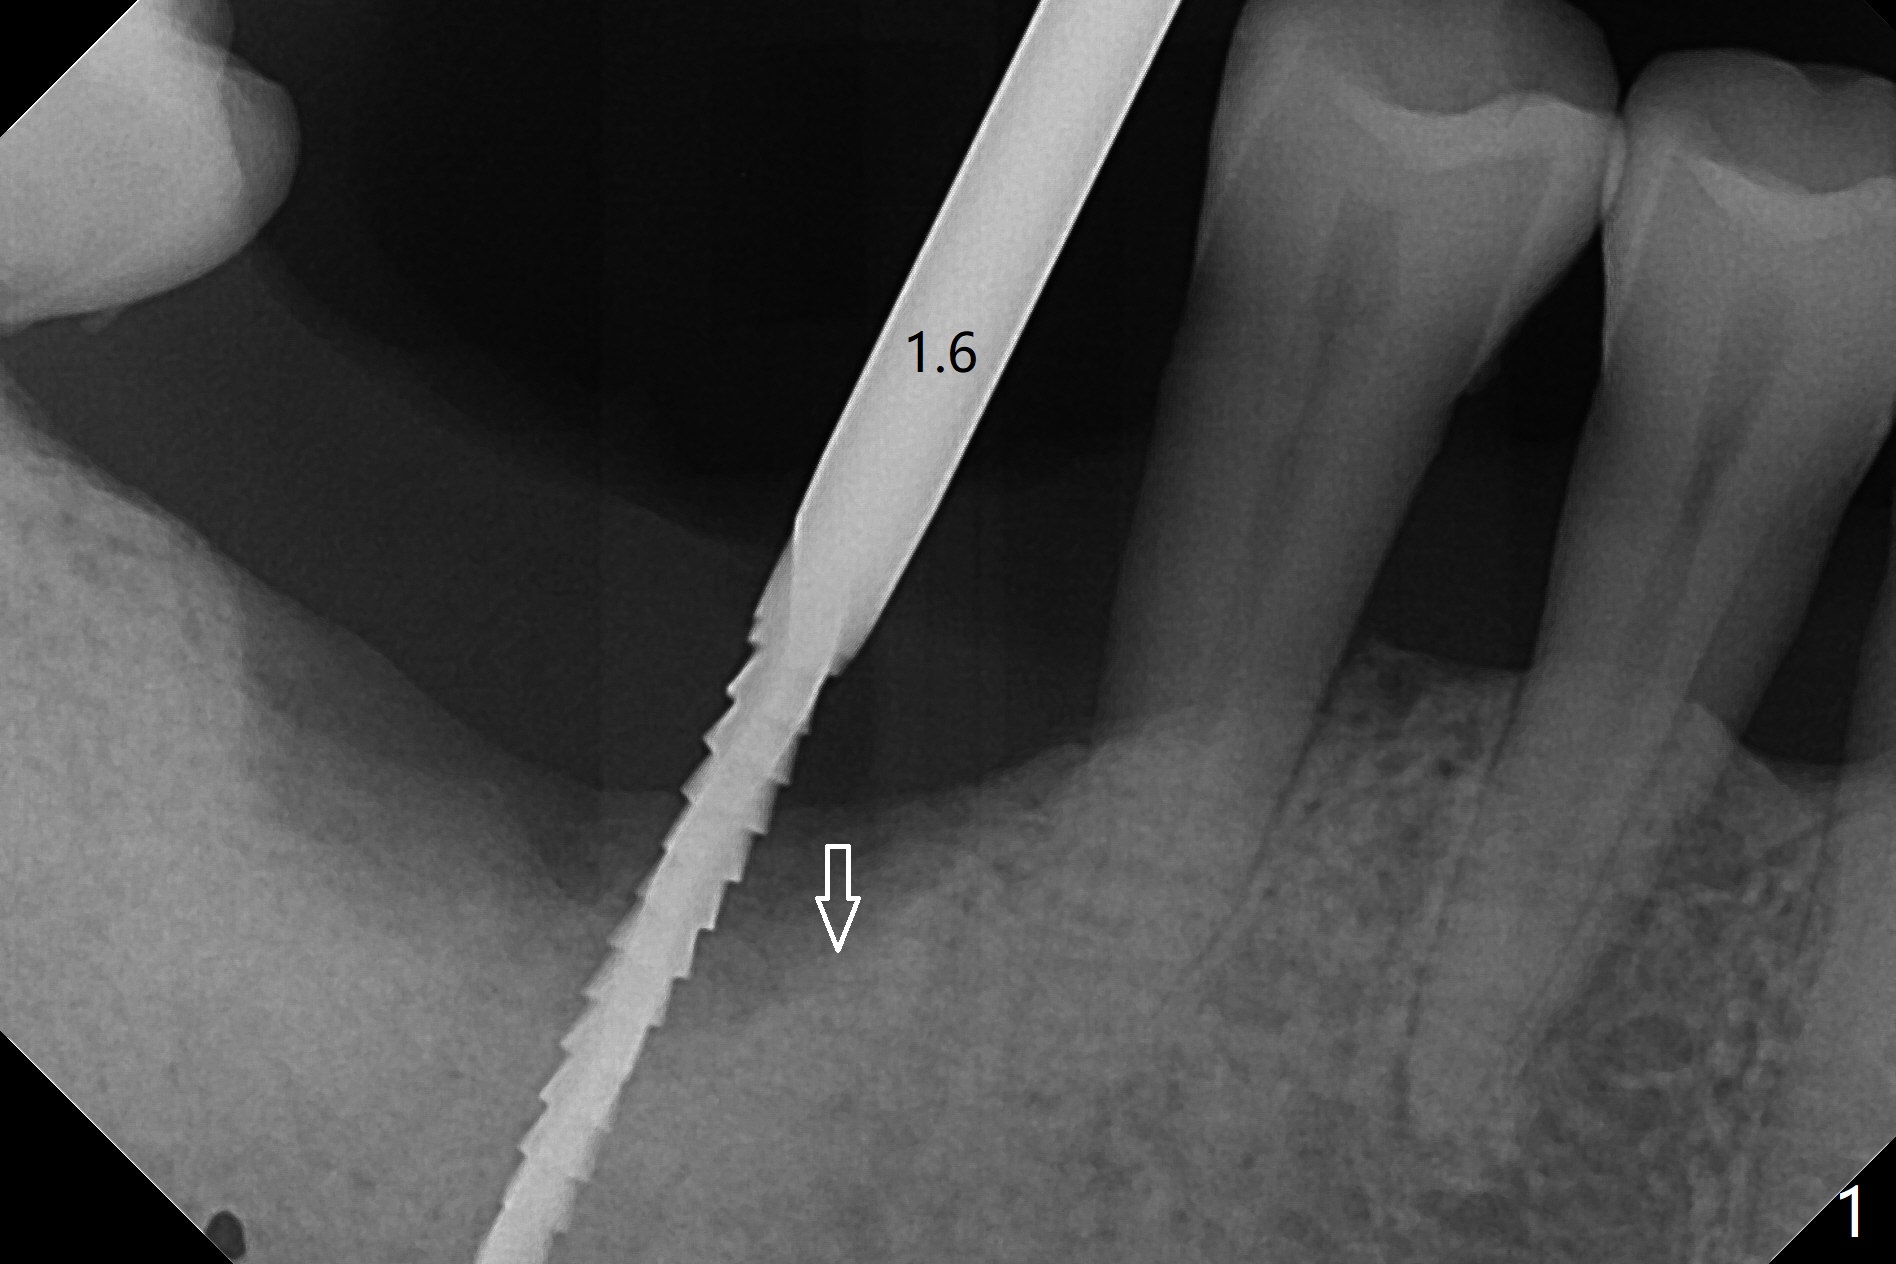

69岁男因疼痛回来拔除右下6,保留中隔牙龈,在近中牙槽窝开始钻洞(图一:空箭头),但是由于近中斜坡,最终1.6毫米先锋钻远中偏移。远中骨质高度减少,原先计划近中牙槽窝深度7毫米,当钻头滑到接近中隔,钻头尖口内接近神经,病人感到疼痛(浸润麻醉)。block anesthesia下,放置4x9毫米报废植体(图二),口内显得太长,所以选择4x7毫米植体(图三),基台就位。第一次放置骨粉远中不足(图四:*),再次植骨,好像达到目的(图五:*)。覆盖PRF膜后,放置树脂敷料(图六:A)。